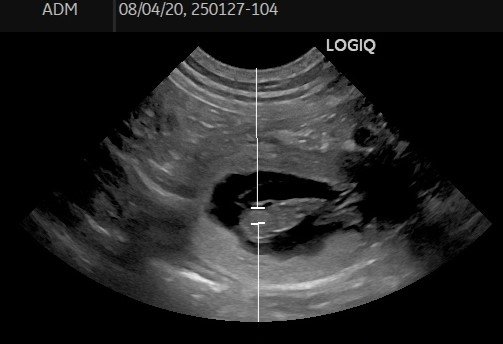

Wir freuen uns riesig, bekanntgeben zu dürfen, dass unsere geliebte "Prinzessin" Maisha tragend ist. Der gestrige Ultraschall (27.01.) hat es bestätigt.

Wir erwarten aus der Verpaarung von Jupp und Maisha Anfang März zauberhafte Welpen 🎉!